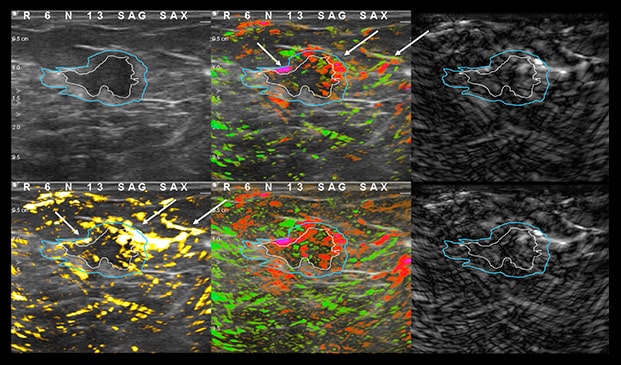

Case Example 5:

59-year-old female presents with a new mammographic asymmetry on the left breast.

A 1.2 cm mass is seen on ultrasound with some doppler signal along periphery of mass.

Case Example 5: Observations

With OA imaging we can see negative internal findings but positive external features in the boundary and peripheral zones.

We can see feeding and draining vessels or “whiskers” in the boundary and peripheral zones on OA.

Radiating vessels continue from the peripheral zone into the boundary zone and count as features in both zones.

Invasive Ductal Carcinoma Grade I

- ER+

- HER2-

- PR-

- Ki67=10%

The mass was up-classified to BI-RADS 5. Unlike TNC, luminal A masses typically present with external features in the boundary and peripheral zones and no OA internal features. Typically, luminal A masses have a low Ki67 and tend to have less internal angiogenesis and deoxygenation.